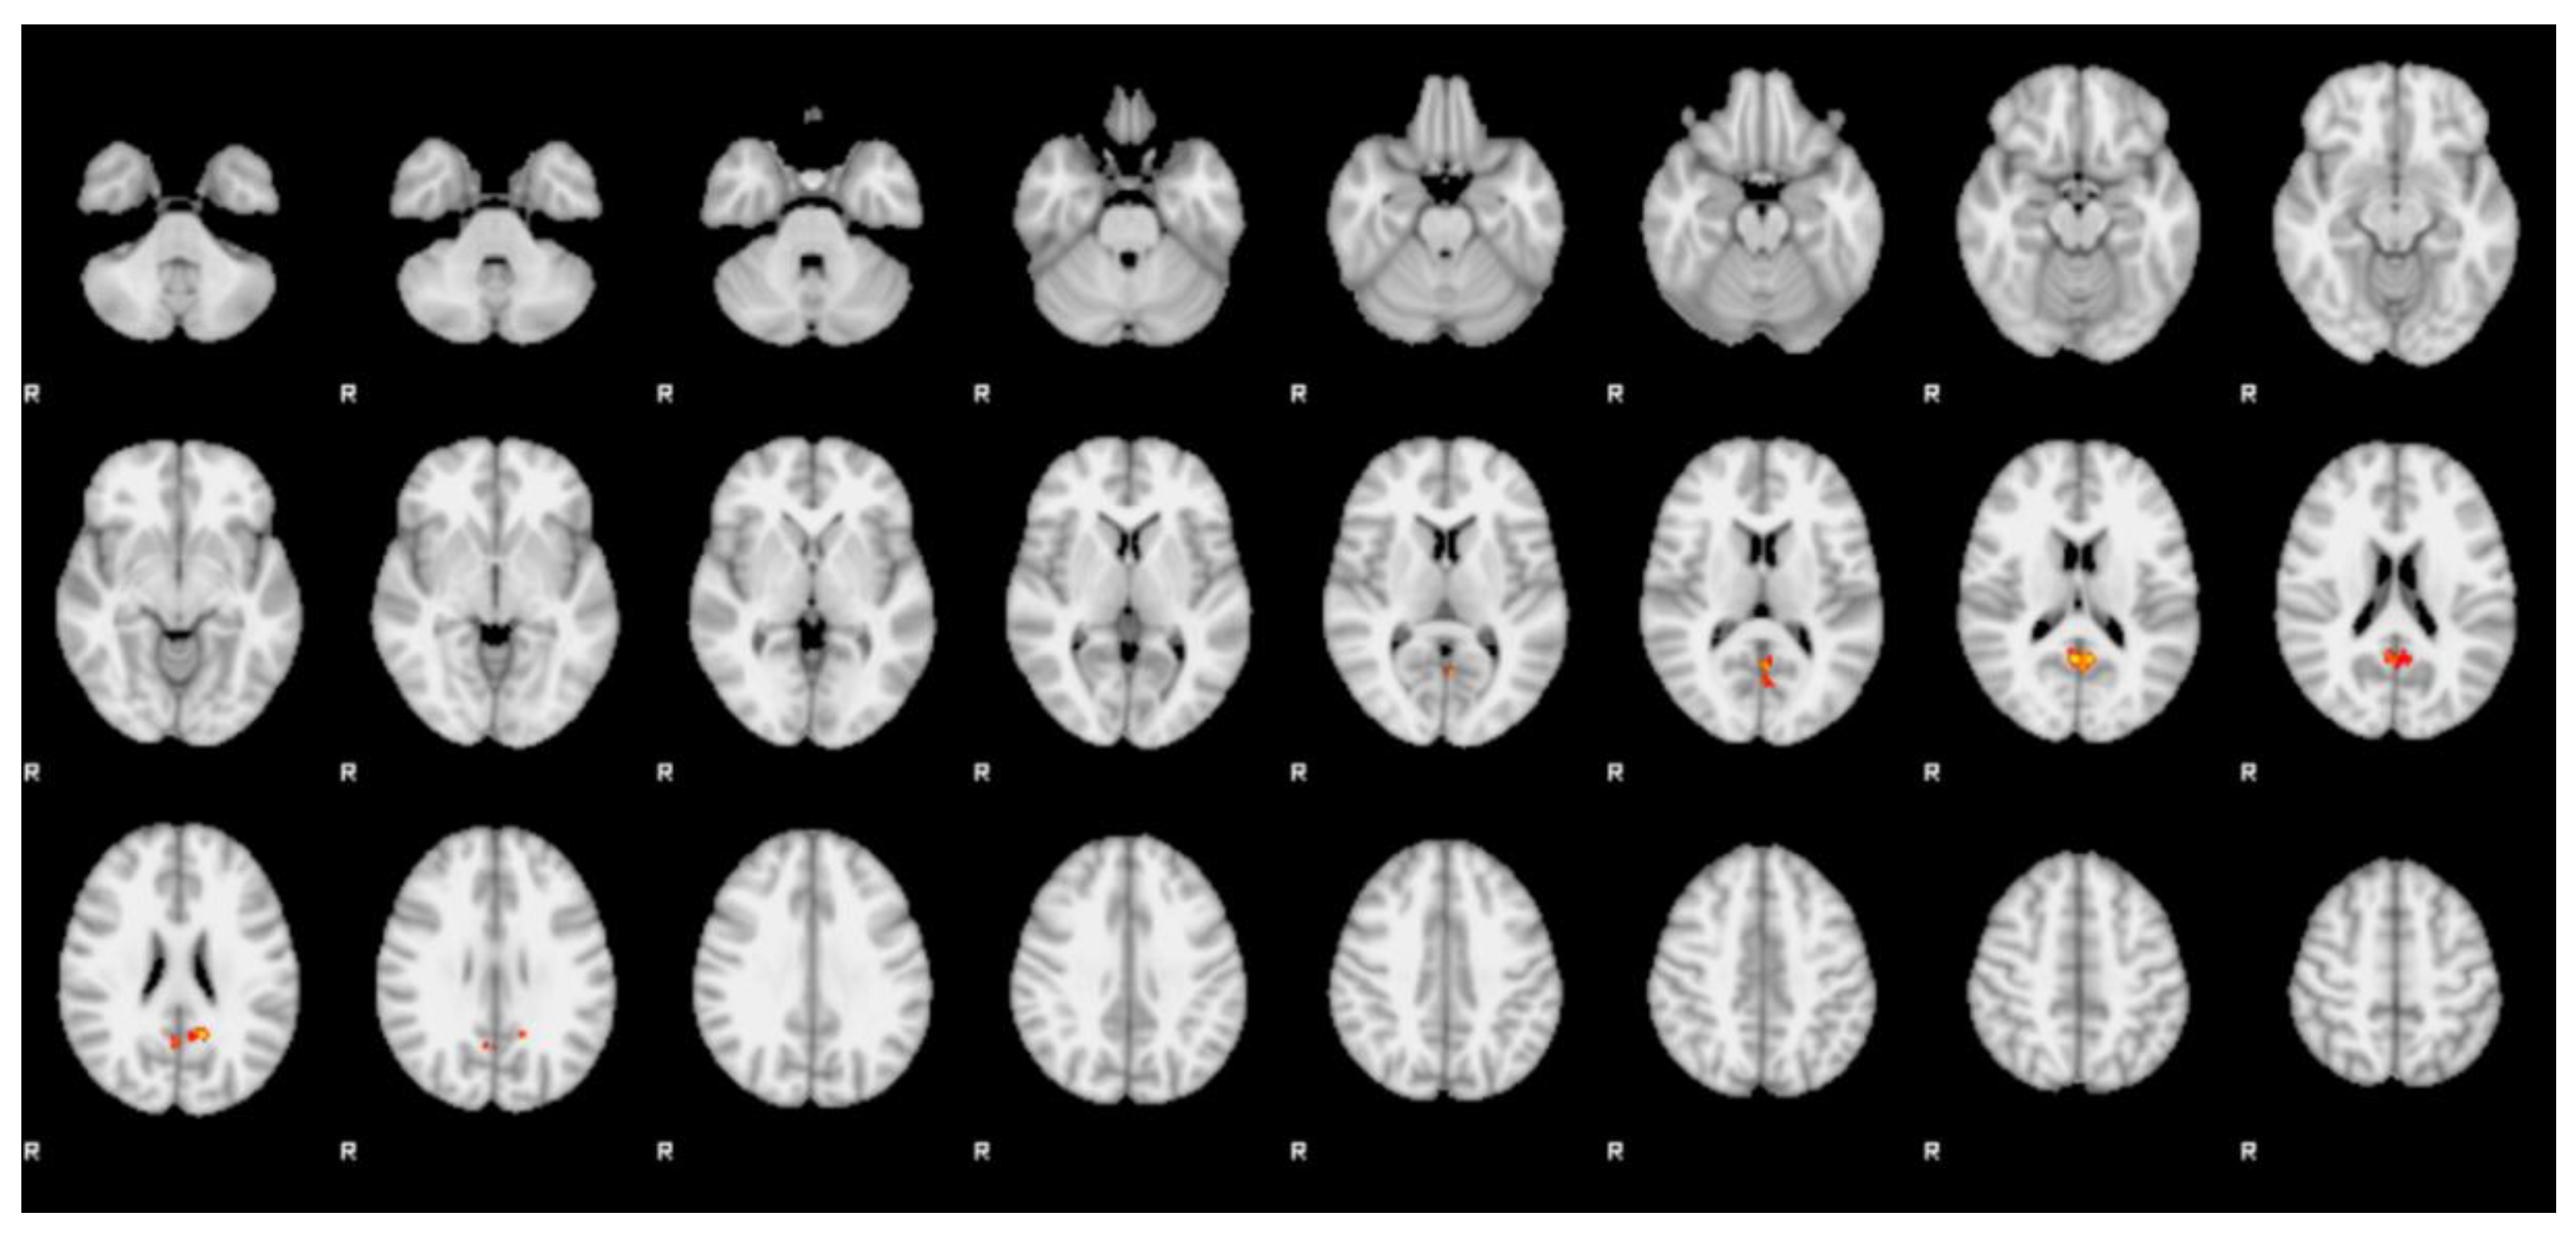

| Cluster | Z-stat | x (mm) | y (mm) | z (mm) | Region (Harvard) |

|---|---|---|---|---|---|

| 1 | 3.01 | −14 | −54 | 26 | left precuneus cortex |

| 3.01 | 0 | −56 | 14 | left precuneus cortex | |

| 3 | −6 | −56 | 16 | left precuneus cortex | |

| 2.89 | −2 | −60 | 16 | left precuneus cortex | |

| 2.82 | −2 | −62 | 8 | left precuneus cortex | |

| 2.74 | 4 | −56 | 22 | right precuneus cortex |